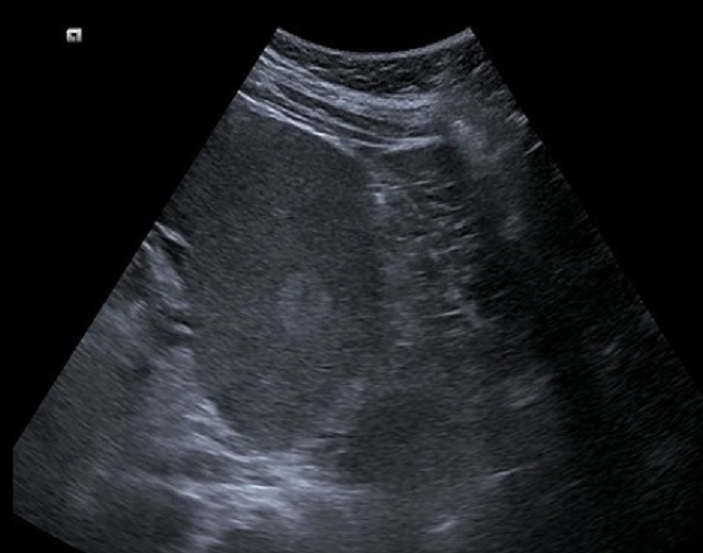

Echographie est la technique

de premiere de l'intention et de choix pour explorer

la splenomegalie . Par cela on peut en verifie la

diametre longitudinal de la rate , elle est grand et

voluminant quand la diametre lonitudinale depasse de

plus > 13cm . On peut en s'observe etat de la

parenchyme et des vaisseaux du hile de la rate |